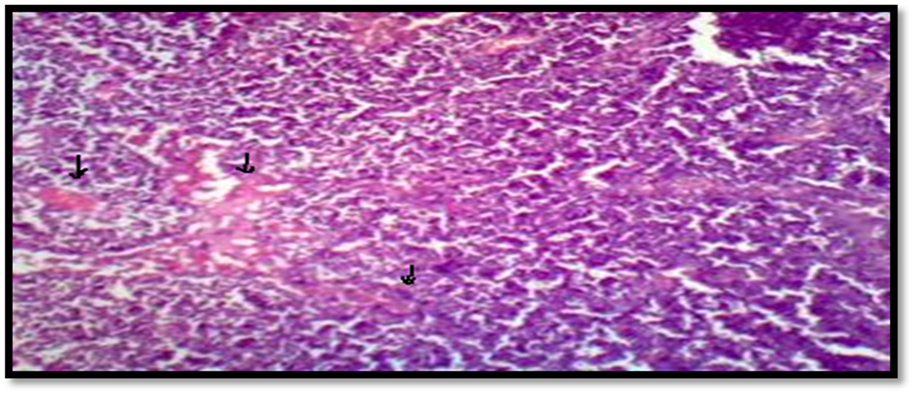

Fig. 13: Sublingual gland of control rat (without drug) with basophilic acinar cells, mucosal cells and Secretory ducts lined by cuboidal epithelium in normal conditions (indicated by arrow)

Fig. 14: Sublingual gland of rat treated with optimized transfersomal sublingual film (TAC_TF_SLF) with basophilic acinar cells, mucosal cells and secretory ducts maintained in comparable good condition (indicated by arrow)

Rats were sacrificed under anesthesia in accordance with all CPSCEA guidelines, and sublingual tissues from Group I and II rats (normal control and O_TAC_TF_SLF) were removed and examined for cell distortion in order to test the irritancy potential of specially formulated, optimized nanovesicular film.

When compared to the normal control group, it was found that all histopathological slides of optimized sublingual films showed basophilic acinar cells, mucosal cells, and secretory ducts of rat sublingual glands in normal condition, ensuring the potency and safety of films.